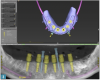

Fig 3. Implant planning for the mandibular arch for the patient of

Case Study 1.

Figure 3

Six implants were planned for both the maxillary and the mandibular arches, respectively (Figure 2 and Figure 3). A dual-arch CBCT was taken (Dentri-Max, HDX WILL; alternatively: CS 9600, Carestream; Explorer PRO, PreXion). The CBCT planning data was sent to the manufacturers to fabricate computer-